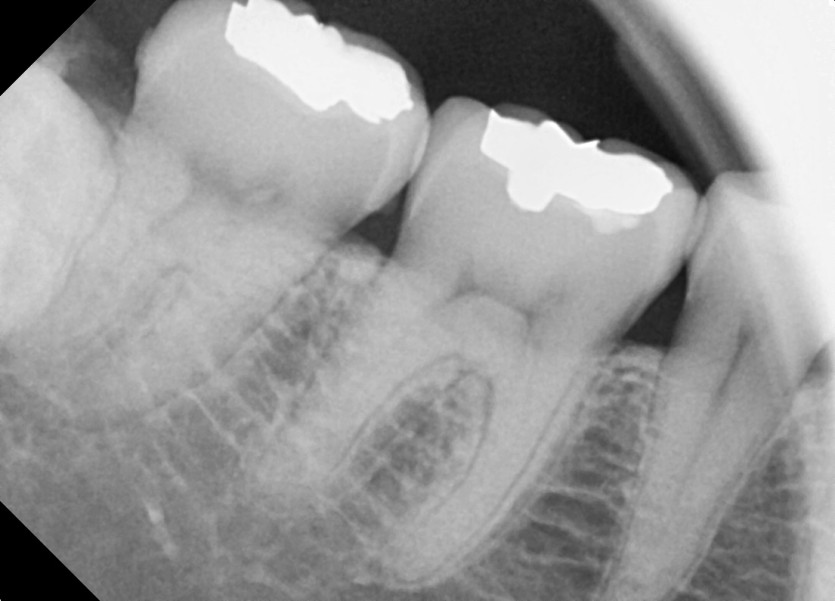

#48 사랑니 발치

구강외과 전문의가 당일발치 했습니다.